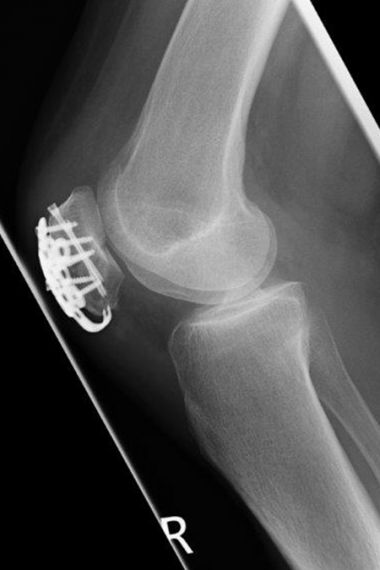

Mehrfragmentärer Kniescheibenbruch nach Sturz, der intraoperativ insbesondere neben quer verlaufenden Brüchen, auch horizontale Bruchkomponenten umfasste. Versorgung mit einer speziellen winkelstabilen Platte. Das Ergebnis zeigt eine sehr gute Funktion mit Wiederherstellung der vollständigen Kniegelenksfunktion.